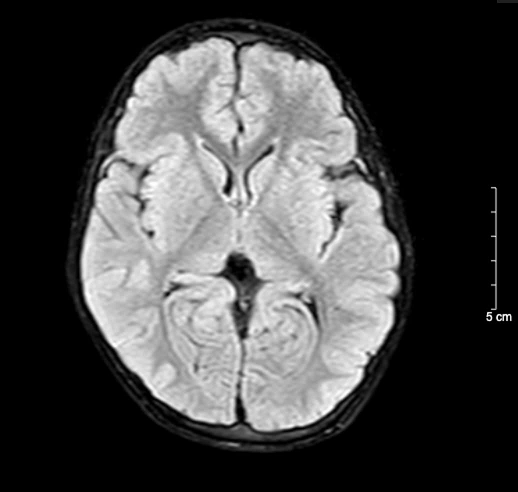

Kết quả chụp não, cột sống cổ bệnh nhi sau 5 ngày nhập viện bình thường

BSCKII. Doãn Phúc Hải – Trung tâm Nhi khoa, Bệnh viện Bạch Mai trực tiếp điều trị cho bệnh nhi chia sẻ: Thân nhiệt của bệnh nhi được hạ nhanh xuống và kiểm soát duy trì ở mức 34°C, giảm tổn thương, tái tưới máu tại não, tăng tỉ lệ sống và hồi phục chức năng thần kinh. Sau 72 giờ điều trị hạ thân nhiệt chủ động, bệnh nhi được nâng thân nhiệt, làm ấm trở lại về mức bình thường và duy trì theo dõi trong 48 giờ. Khi thân nhiệt trở lại bình thường, bệnh nhi tỉnh dần và được rút ống thở. Dấu hiệu sinh tồn ổn định, tri giác nhận thức tốt. Sau 5 ngày nằm viện, bệnh nhi đã tỉnh táo hoàn toàn. Kết quả chụp tim, phổi, MRI sọ não, cột sống cổ không thấy bất thường. Đây cũng là trường hợp đầu tiên trẻ 5 tuổi tự “thắt cổ” mà chúng tôi bắt gặp.